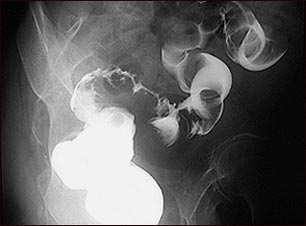

Rayos X de cáncer de colon sigmoide

Enema de bario en un paciente con cáncer del intestino grueso (área sigmoide).